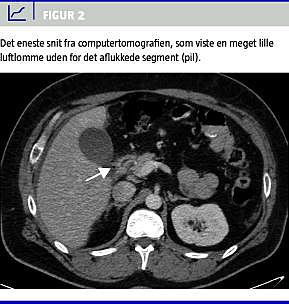

Ved første gennemgang af CT-billederne kunne radiologen ikke påvise fri intraperitoneal luft, men efter information om operationsfundet kunne man på et af transversalbillederne se en yderst diskret lille luftlomme umiddelbart uden for det aflukkede segment (Figur 2 ).

Patienterne har som andre patienter med nyanlagte anastomoser risiko for anastomoselækage, specielt i de første to uger postoperativt. Gastrisk blowout og intern herniering er komplikationer, der især er relateret til RYGBP-operation. Disse komplikationer er ligesom anastomoselækage alvorlige og kan indtræffe fra umiddelbart efter operationen til flere år efter det operative indgreb. En særlig diagnostisk udfordring hos RYGBP-opererede patienter er en perforation i enten duodenum eller den udshuntede ventrikel. Diagnostikken vanskeliggøres af, at luften i det aflukkede segment bliver absorberet efter RYGBP-operationen [3]. Herefter kommer der ikke større mængder luft til dette stykke af tarmsystemet. Ved perforationer i det aflukkede segment ses der derfor sjældent fri intraperitoneal luft på røntgenbilleder [2].